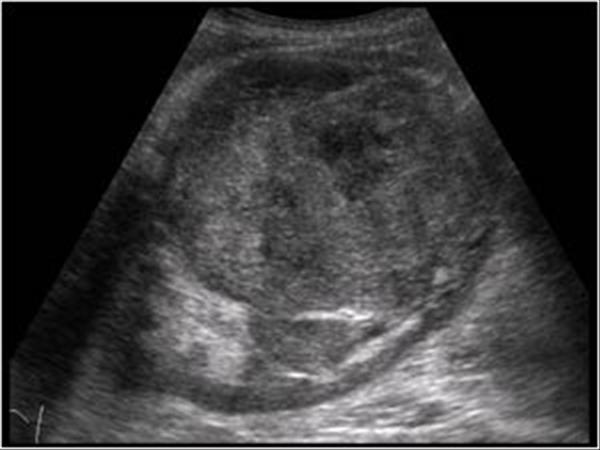

# Ung thư biểu mô tế bào thận phải (Renal cell carcinoma – RCC) / Huyết khối tĩnh mạch chủ dưới.